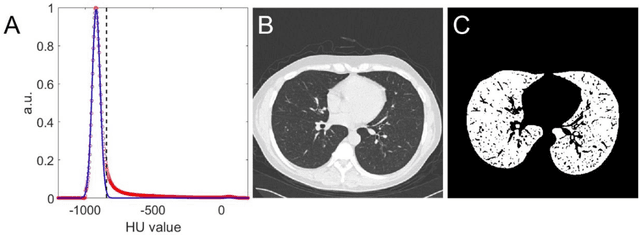

Abstract:Background: Triage of patients is important to control the pandemic of coronavirus disease 2019 (COVID-19), especially during the peak of the pandemic when clinical resources become extremely limited. Purpose: To develop a method that automatically segments and quantifies lung and pneumonia lesions with synthetic chest CT and assess disease severity in COVID-19 patients. Materials and Methods: In this study, we incorporated data augmentation to generate synthetic chest CT images using public available datasets (285 datasets from "Lung Nodule Analysis 2016"). The synthetic images and masks were used to train a 2D U-net neural network and tested on 203 COVID-19 datasets to generate lung and lesion segmentations. Disease severity scores (DL: damage load; DS: damage score) were calculated based on the segmentations. Correlations between DL/DS and clinical lab tests were evaluated using Pearson's method. A p-value < 0.05 was considered as statistical significant. Results: Automatic lung and lesion segmentations were compared with manual annotations. For lung segmentation, the median values of dice similarity coefficient, Jaccard index and average surface distance, were 98.56%, 97.15% and 0.49 mm, respectively. The same metrics for lesion segmentation were 76.95%, 62.54% and 2.36 mm, respectively. Significant (p << 0.05) correlations were found between DL/DS and percentage lymphocytes tests, with r-values of -0.561 and -0.501, respectively. Conclusion: An AI system that based on thoracic radiographic and data augmentation was proposed to segment lung and lesions in COVID-19 patients. Correlations between imaging findings and clinical lab tests suggested the value of this system as a potential tool to assess disease severity of COVID-19.